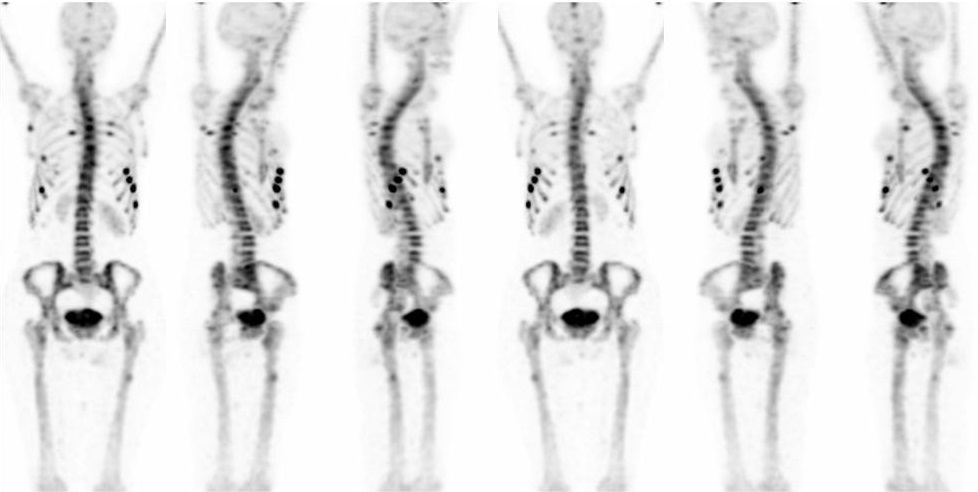

Douleurs costales et sternales sans notion traumatique chez une patiente de 39 ans.

Multiples foyers fissuraires au niveau du gril costal, de la scapula gauche et du fémur droit (aspect de strie de Looser-Milkmann).

Calcifications méningées aux niveaux de la faux du cerveau et de la moëlle à l’étage thoracique.

Ostéomalacie.